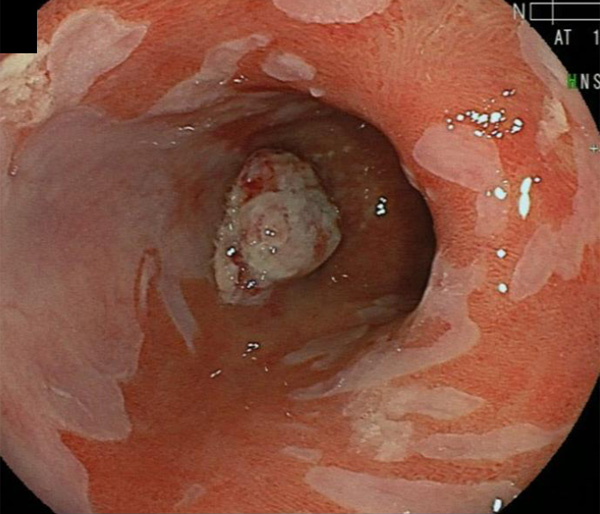

2026年1月24日開催の第19回研究会でご提示した検討症例です。 (画像をクリックすると拡大します)

2025年7月19日開催の第18回研究会でご提示した検討症例です。 (画像をクリックすると拡大します)

2025年1月11日開催の第17回研究会でご提示した検討症例です。 (画像をクリックすると拡大します)

2024年6月29日開催の第16回研究会でご提示した検討症例です。 (画像をクリックすると拡大します)

2024年1月6日開催の第15回研究会でご提示した検討症例です。 (画像をクリックすると拡大します)

2023年7月1日開催の第14回研究会でご提示した検討症例です。 (画像をクリックすると拡大します)

2023年1月21日開催の第13回研究会でご提示した検討症例です。 (画像をクリックすると拡大します)

2022年7月2日開催の第12回研究会でご提示した検討症例です。 (画像をクリックすると拡大します)

2022年1月22日開催の第11回研究会でご提示した検討症例です。 (画像をクリックすると拡大します)

2021年6月26日開催の第10回研究会でご提示した検討症例です。 (画像をクリックすると拡大します)

2021年1月23日開催の第9回研究会でご提示した検討症例です。 (画像をクリックすると拡大します)

2020年1月25日開催の第8回研究会でご提示した検討症例です。 (画像をクリックすると拡大します)

2019年1月12日開催の第6回研究会でご提示した検討症例です。 (画像をクリックすると拡大します)

2018年6月30日開催の第5回研究会でご提示した検討症例です。 (画像をクリックすると拡大します)

2017年7月15日開催の第3回研究会でご提示した検討症例です。 (画像をクリックすると拡大します)

2017年1月7日開催の第2回研究会でご提示した検討症例です。 (画像をクリックすると拡大します)

2016年6月4日開催の第1回研究会でご提示した検討症例です。 (画像をクリックすると拡大します)